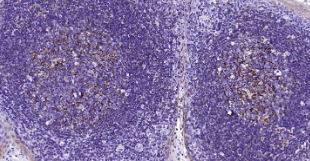

Immunohistochemical analysis of paraffin embedded human tonsil tissue slide using IHC0234H (Human CD21 IHC Kit).